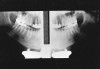

The top radiograph in Figure 23 is a normal panograph. The bottom panograph is one that was affected by short-duration movement. Notice how the patient’s left mandible appears to be notched along the upper margin. The notch could easily be interpreted as calcification at an old fracture site when, in reality, it is a movement artifact. Remember, when viewing radiographs, the patient’s left is on the viewer’s right.

Figure 23. Panoramic films - top-normal; bottom - showing movement.

Figure 23